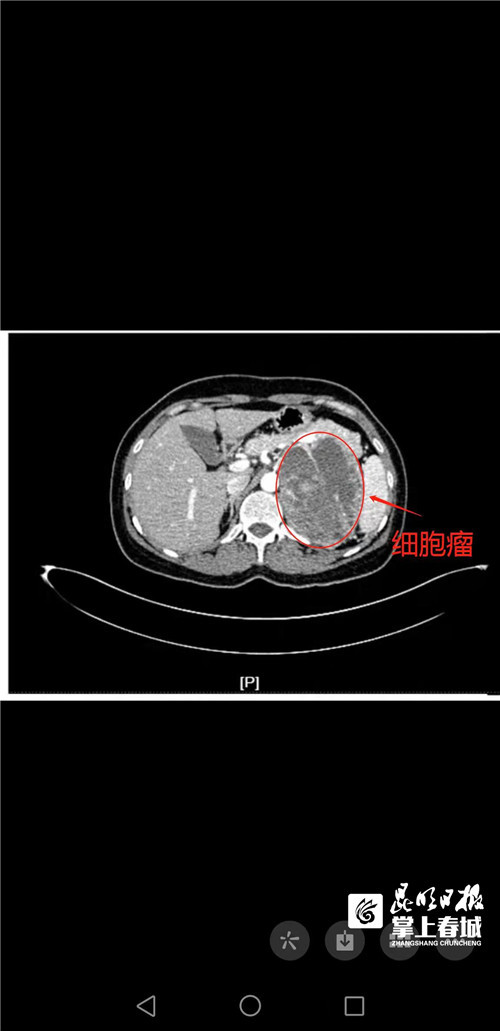

厉兵秣马术前准备15天 医生1小时摘除巨大肾上腺嗜铬细胞瘤

图片尺寸500x1031